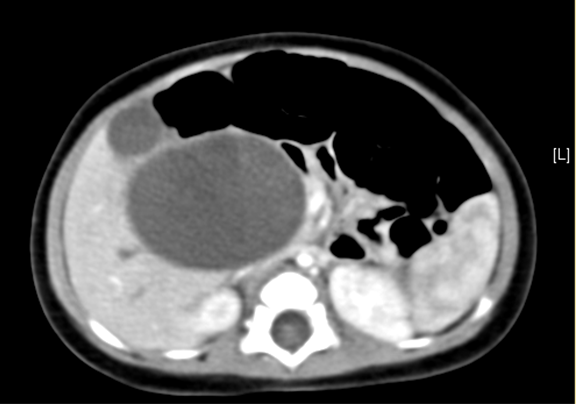

上腹部增强CT:先天性胆管扩张症(胆总管囊肿)可能性大。

术前CT检查:

动脉期

静脉期

平衡期